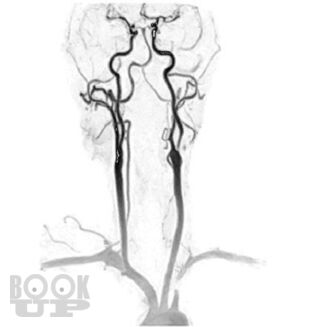

В пособии представлен не только хирургический раздел, но и анатомия кровообращения головного мозга и неврологическая симптоматика цереброваскулярных нарушений при атеросклеротических каротидных поражениях, поскольку каротидная хирургия неразрывно связана с этими аспектами. Приводится алгоритм обследования больных, охватывающий все современные методы нейровизуализации с указанием уровней доказательности, чувствительности и специфичности каждого из них. Особый акцент сделан на ценности ультразвуковых методов, которые наиболее доступны в клинической практике и достаточно информативны. При изложении лучевой семиотики для иллюстрации основных ангиоморфологических изменений даны эходопплерограммы, ангиограммы. Подробно описаны показания к хирургическому лечению, различные методы реконструкции сонных артерий.